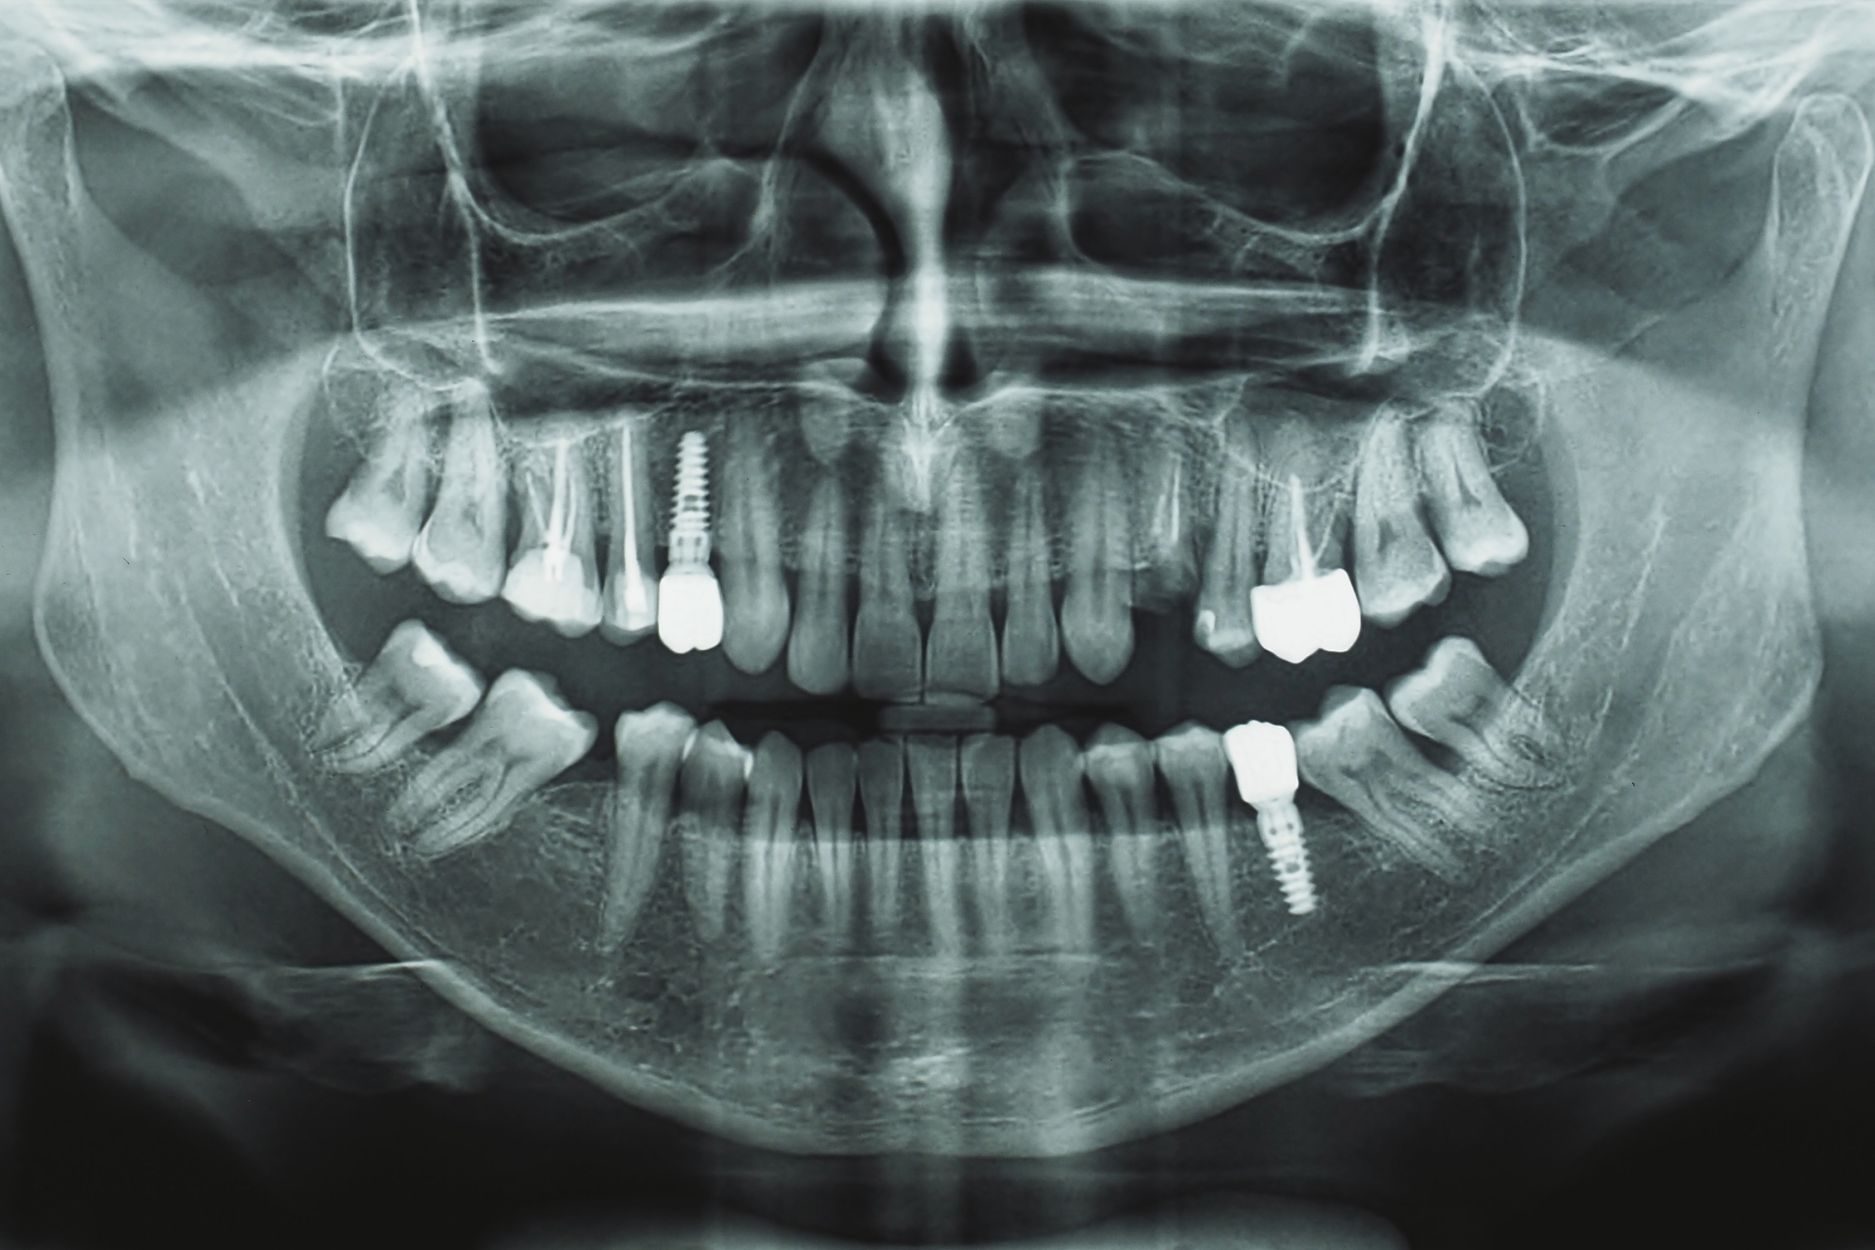

Maxillofacial surgery at Alma Polyclinic, performed by an oral and maxillofacial surgeon in Dubai, focuses on treating diseases, injuries, and defects in the neck, face, jaws, and the hard and soft tissues of the oral and maxillofacial region. This specialized surgery can address a wide range of conditions, from impacted teeth, facial pain, and TMJ disorders to more complex craniofacial cases such as cleft lip and palate, and fractures of the facial skeleton. The expertise of an oral and maxillofacial surgeon is crucial not only for the functional restoration of these areas but also for enhancing aesthetic appearance, thereby significantly improving patients’ quality of life and self-confidence.

Additionally, dental implant surgery is available for those seeking to restore missing teeth with durable, natural-looking replacements. For patients experiencing facial or dental disorders, our targeted treatments aim to relieve pain and restore mobility.